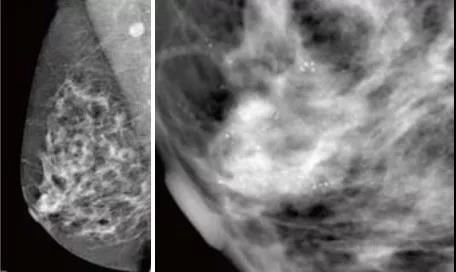

GE 平板數(shù)字乳腺機(jī)拍攝的右乳MLO,清晰顯示早期乳腺癌的沙粒樣鈣化,

此時(shí)乳腺觸診并沒(méi)有任何異常